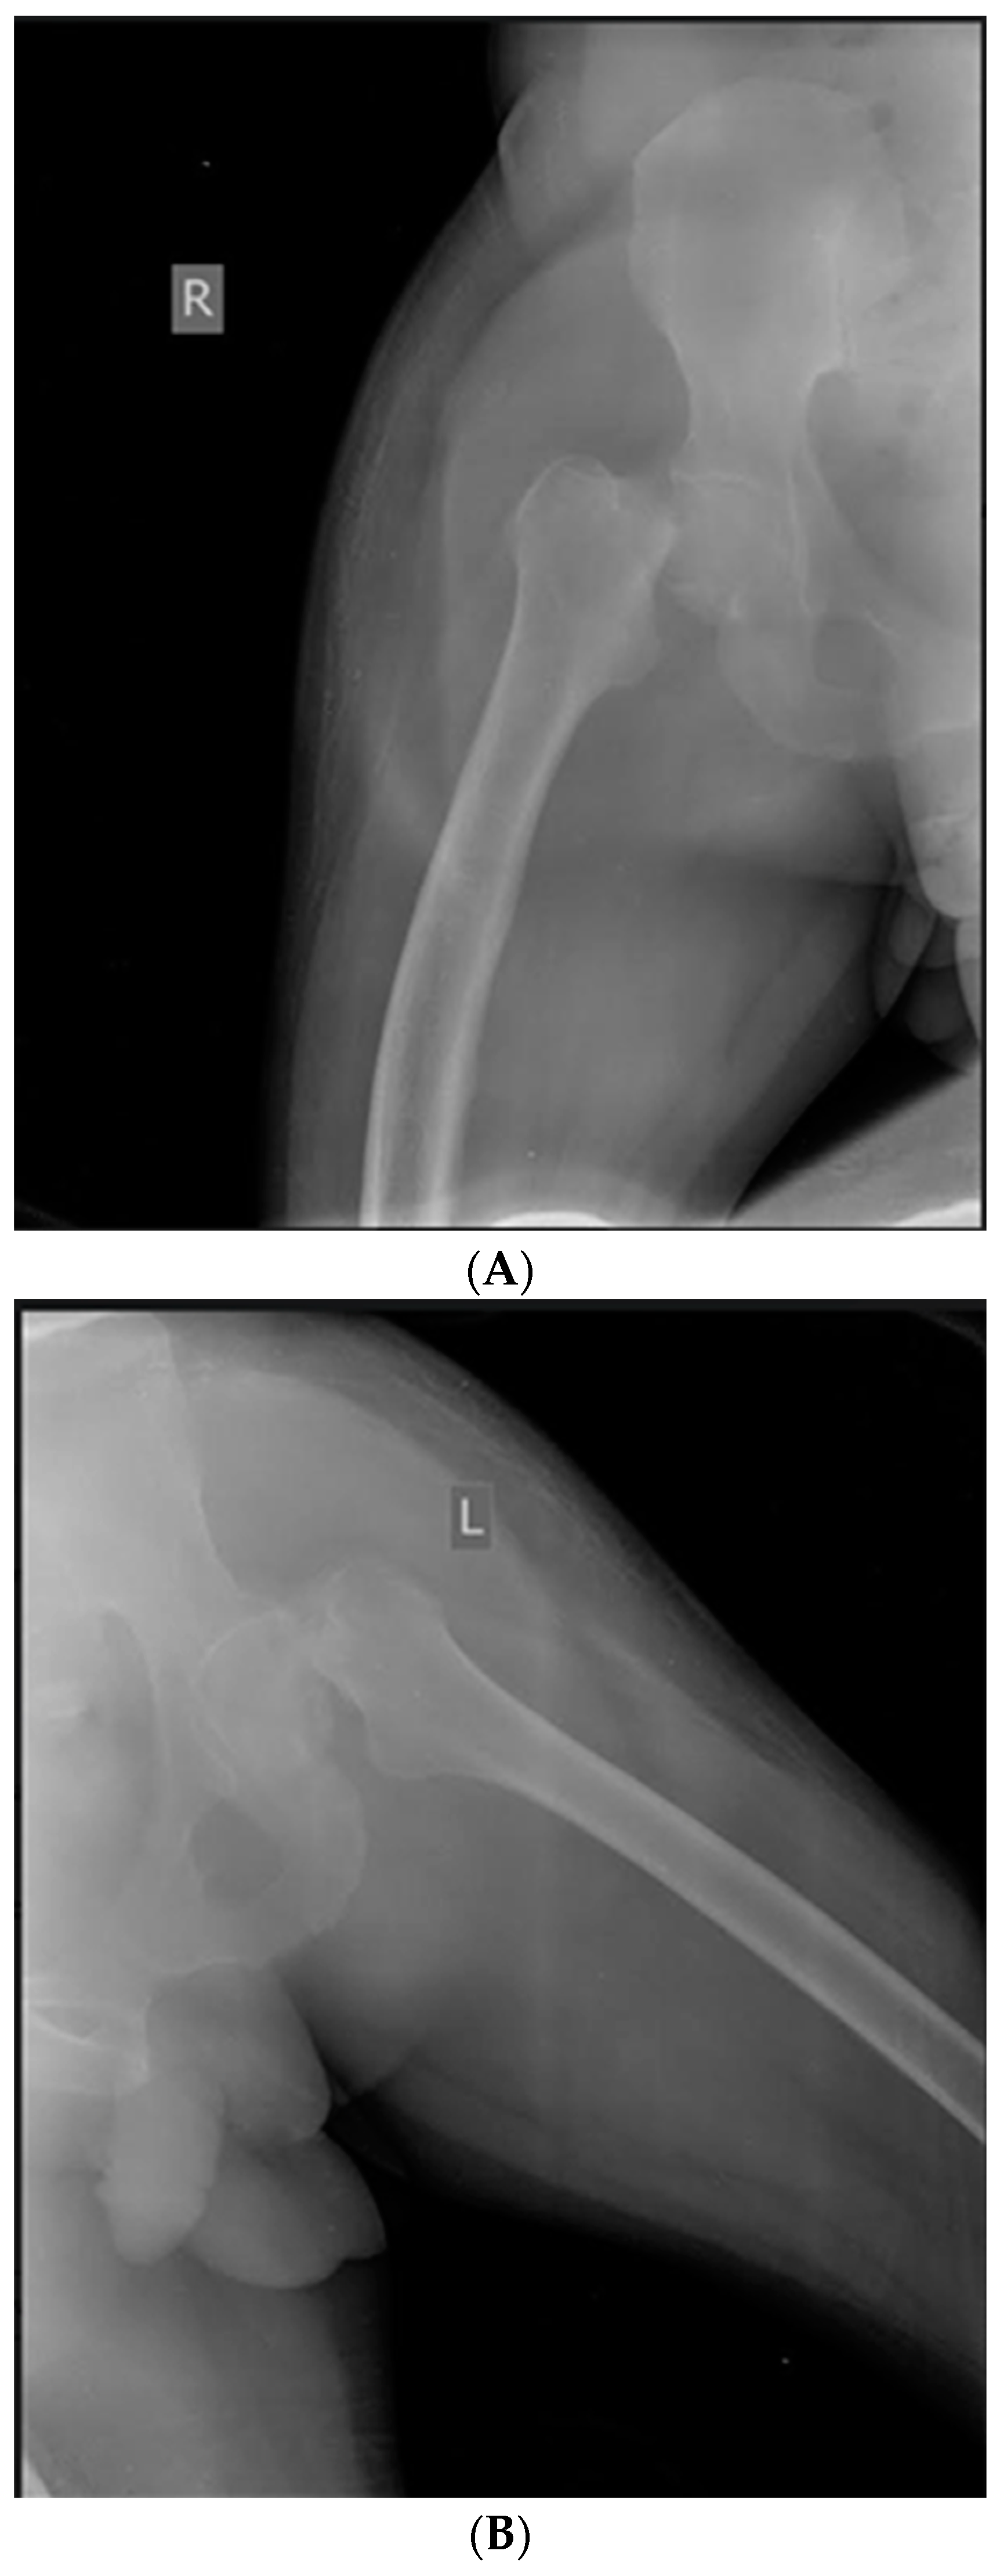

| Case 1. 50-years-old male, with severe haemophilia B | -known and treated for epilepsy -chronic viral hepatitis C | -trauma-related bilateral femoral neck fracture | -bilateral simultaneous hip arthroplasty -the right hip joint is complicated with pertrochanteric fracture, needing an additional osteosynthesis with screws | ~1200 mL (3 units pRBCs) | ~86,856.05 € (91.75% for recombinant FIX concentrate) | No | Good, discharged after 30 days |